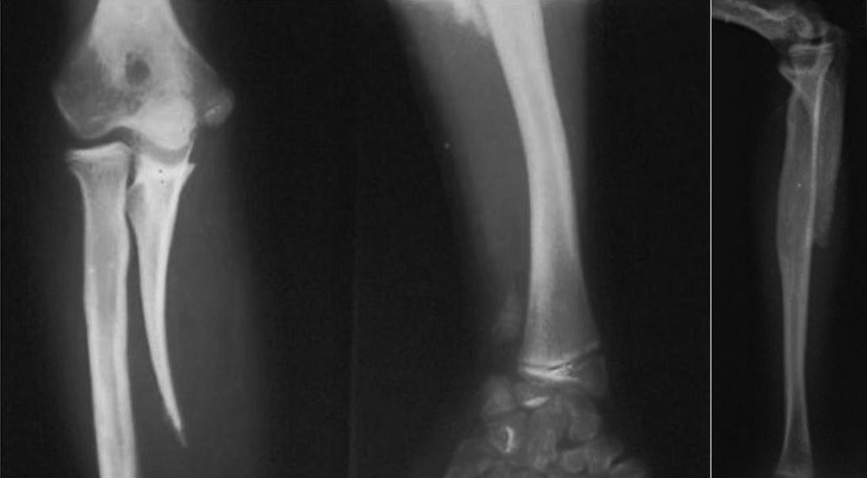

The fifth patient was a 6-year-old boy with type 2B deficiency (ulnar hypoplasia with present proximal and distal epiphysis and wrist amputation) of the affected right arm. The right elbow was functional. Radiographs indicated a hypoplastic ulna with negative ulnar variance and congenital wrist amputation (Figure 5).

The sixth patient was a 28-year-old man with type 2C deficiency (ulnar hypoplasia with present proximal and distal epiphysis, a dislocated radial head, and bowed radius). Radiographs of the affected right arm showed bowing of the radius, dislocation of the radiohumeral joint, subluxation of the wrist with ulnar deviation, and reduced longitudinal growth of the radius. The findings indicated that the fibrocartilaginous ulnar anlage may have been the anatomic structure responsible for the deformities (Figure 6).

The seventh patient was a 13-year-old girl with type 3 deficiency (partial aplasia of the central and distal diaphysis of the ulna) of the affected right arm. The patient had a functional extremity, a normal hand, and a stable wrist and elbow. Radiographs showed partial aplasia of the ulna involving the middle and distal diaphysis with a hypoplastic distal metaphysis and epiphysis. There was negative ulnar variance but no deficiencies of the wrist and hand. The proximal part of the ulna was not hypoplastic, and the radius was straight (Figure 7).